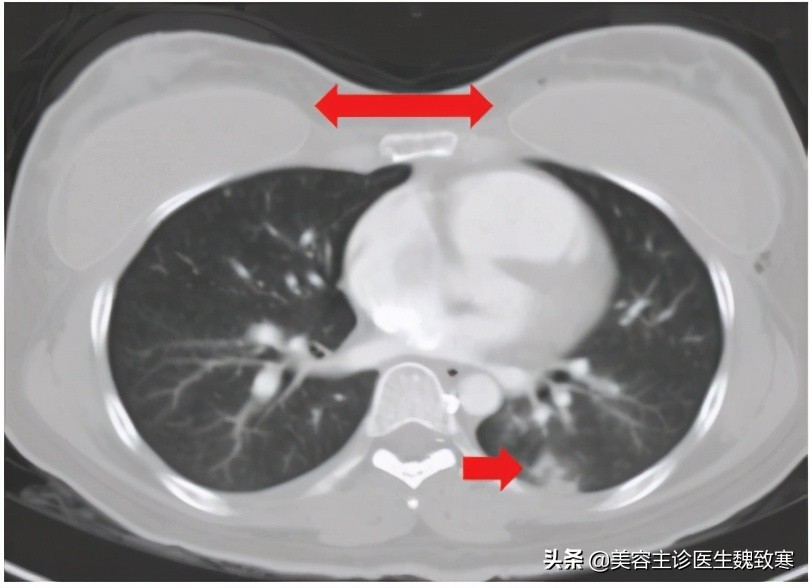

图1

患者无吸烟或饮酒史,胸部听诊显示肺部大部分为双侧湿罗音。胸部计算机断层扫描(CT)显示左肺下叶局部渗出(见上图1),右心房(图2A)和心室增大,双侧下叶动脉发育不均伴充盈缺损(图2B)。